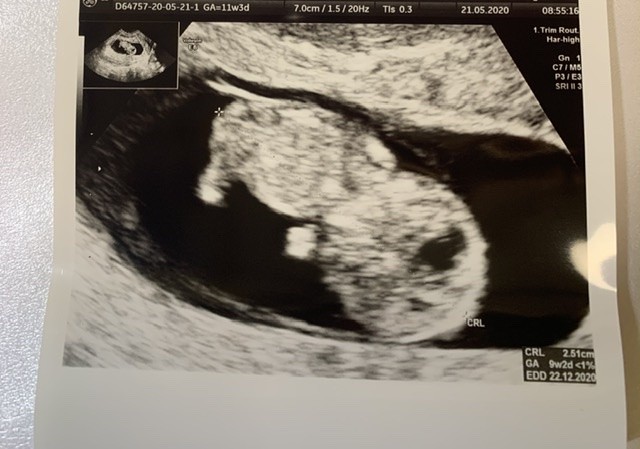

Super przepiękne zdjęcieOd rana czułam się fatalnie i miałam takie przeczucie ze dzieje się coś niedobrego... spanikowałam i pojechałam do ginekologa. Jestem już po badaniu. Fasolka cała i zdrowa serduszko 180. Wrzucam moje 2,5cm szczęścia

Według OM powinien być 11 ale okazuje się ze owulacja spóźniła mi się dwa tygodnie wiec jestem 9+2Super przepiękne zdjęcieA w którym tyg jesteś?